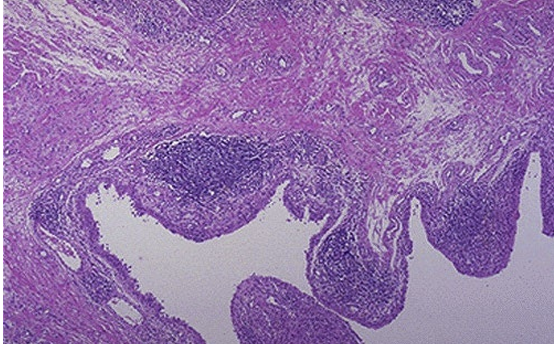

What condition is this from what disease

insulitis in T1D